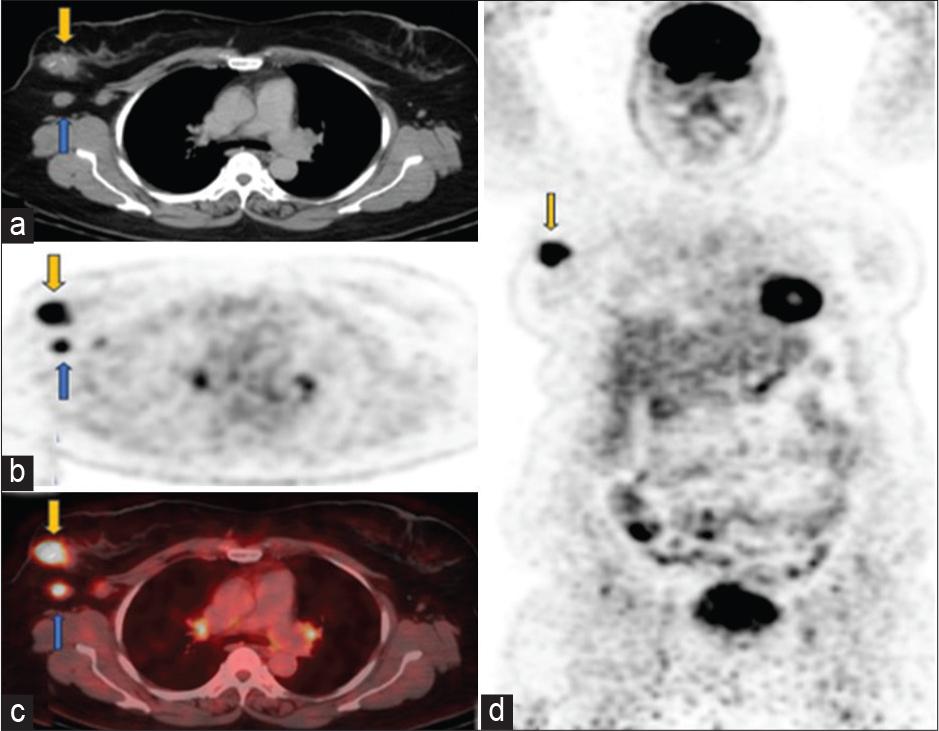

Baseline scan April 2023 (a) axial computed tomography (CT), (b) positron emission tomography only, (c) fused positron emission tomography-CT images through the chest showed fludeoxyglucose (FDG) avid soft tissue mass in the upper outer quadrant of right breast (yellow arrow) has SUV 7.4. FDG avid right axillary lymph nodes (SUV 3.7) are marked with blue arrows, consistent with DLBCL. Small volume mildly avid mediastinal and hilar lymph nodes are likely reactive. (d) Coronal positron emission tomography-only images show hypermetabolic right breast biopsy-proven ductal carcinoma in situ